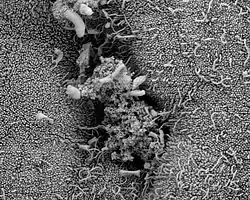

Строение